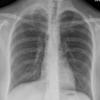

Lymphoma PA (DLBC)

Date: 04/25/2009

Views: 3552